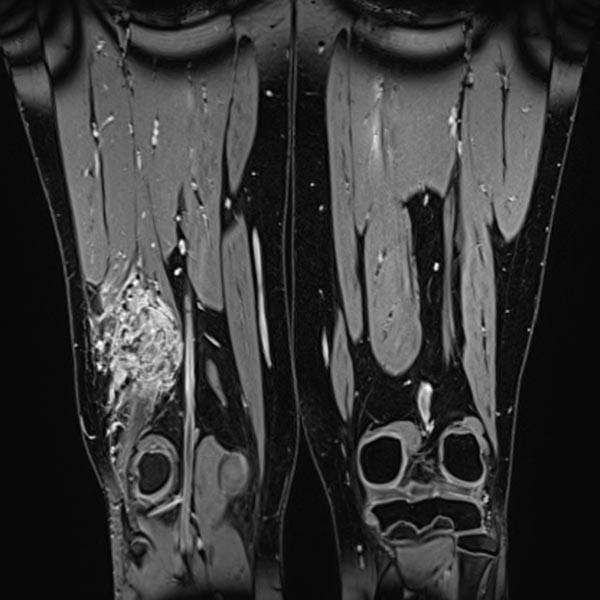

Die koronare, fettunterdrückte T2-Wichtung der Oberschenkel zeigt rechts die intramuskulär gelegene venöse Malformation.

Die T2-gewichtete MRT ohne Fettunterdrückung in axialer Schnittführung offenbart den entzündlichen, fibrotischen Umbau der Läsion durch multiple Entzündungen. Der rechte M. vastus lateralis des M. quadrizeps femoris ist komplett durchsetzt.

Die dynamische MR-Angiographie 62 s nach Injektion des Kontrastmittels zeigt ein langsames pooling des Kontrastmittels in der Läsion ohne frühen venösen Rückstrom (Slow-flow-Malformation). Die Läsion steht in Verbindung mit dem tiefen Leitvenensystem (Kommunikationsvenen).

Die VM nimmt komplett Kontrastmittel auf (MRT in T1-Wichtung, fettgesättigt). Damit entfällt die differentialdiagnostische Erwägung einer lymphatischen Malformation.